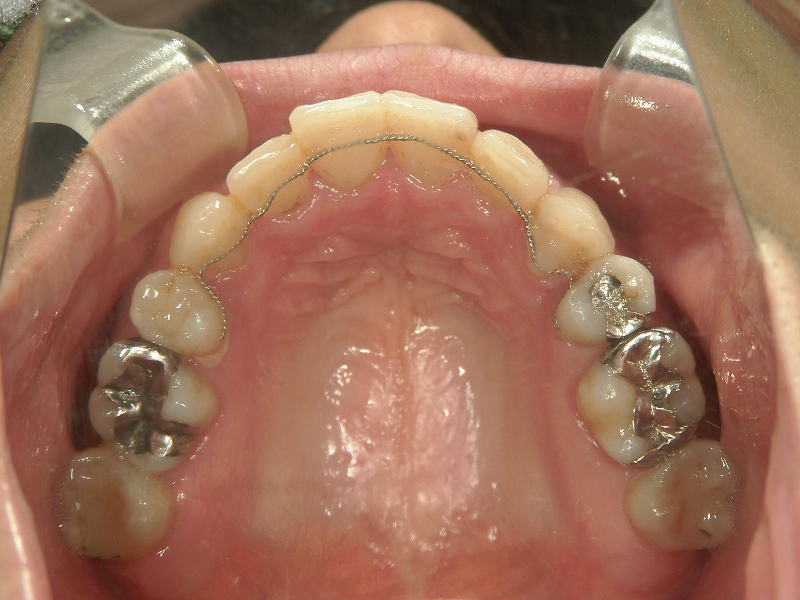

矯正歯科 治療後

矯正_灰色.pngno.31_1962_治療後_上.JPG矯正_灰色.png